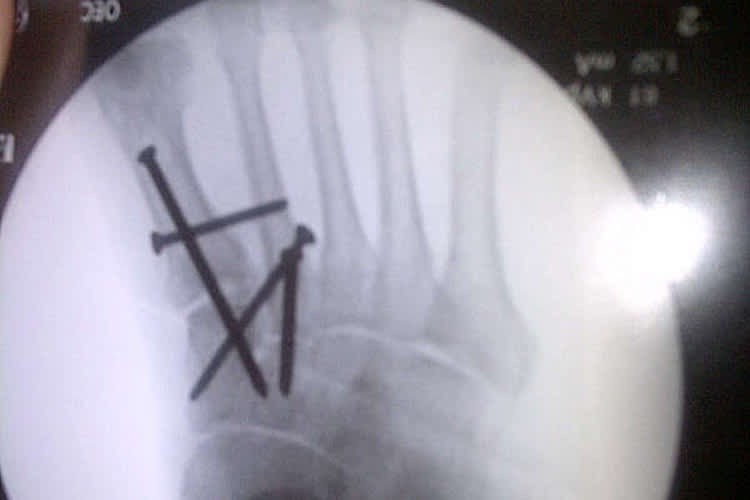

Kenan Sofuoglu wird beim morgigen Indianapolis-GP fehlen. Der Türke brach sich im zweiten freien Training am Freitag nach einem Highsider mehrere Mittelfussknochen rechts.

Weil sich die Knochen übereinandergeschoben haben, wurde der Technomag-CIP-Pilot noch am selben Tag im Krankenhaus von Indianapolis operiert. Insgesamt vier Nägel mussten eingesetzt werden, um alle Knochen zu fixieren. Sofuoglu kämpft nun darum, nächstes Wochenende in Misano wieder dabei zu sein.